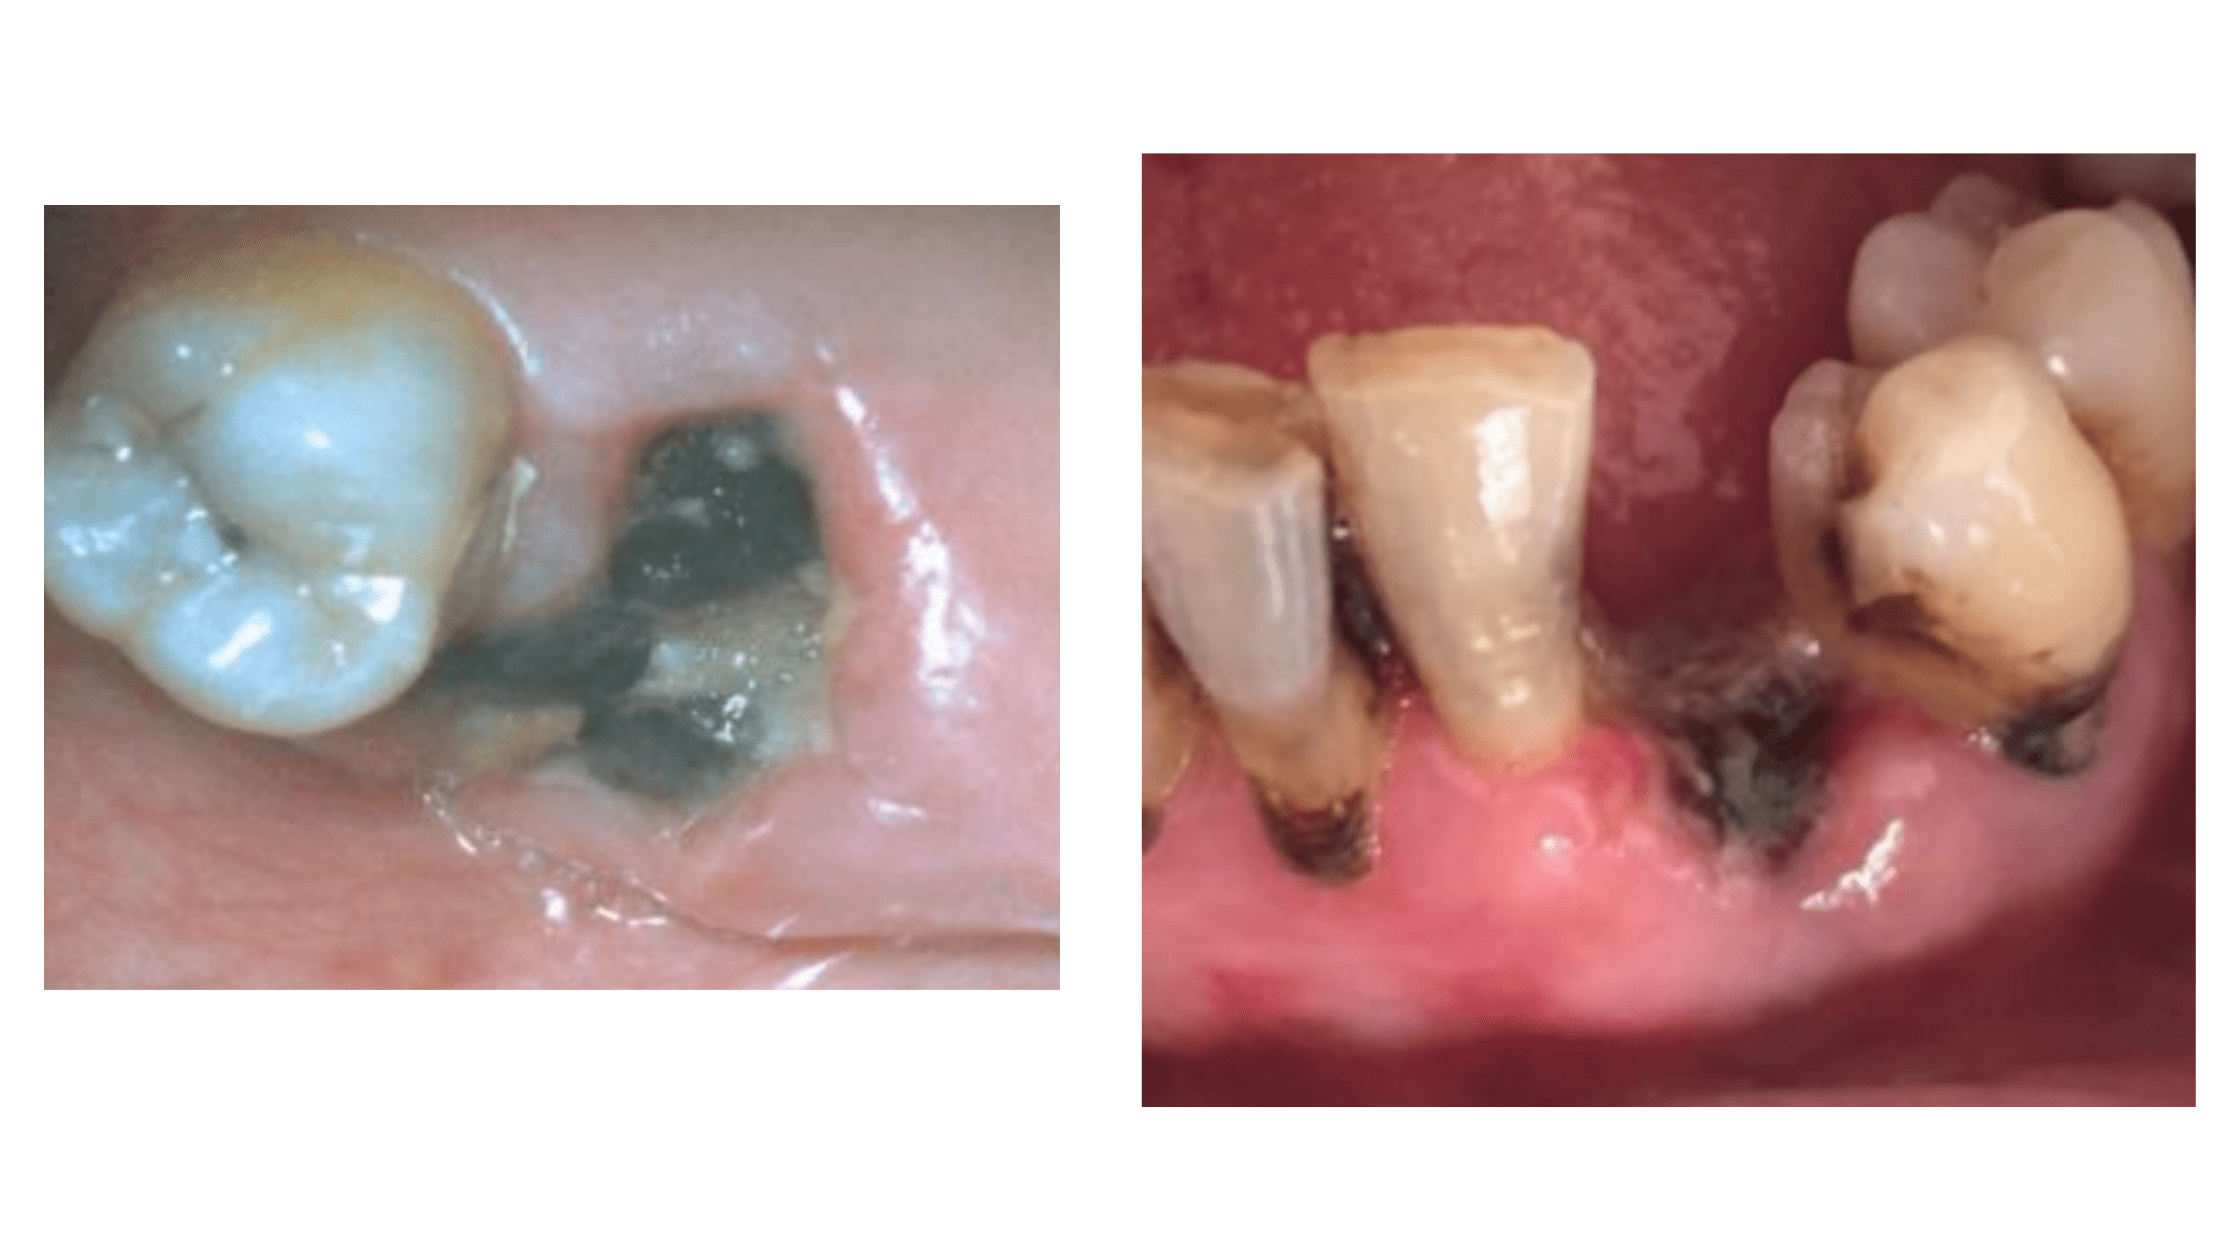

Dry Socket The Most Common Complication After Tooth Extraction

Socket Infection After Tooth Extraction What You Should Know